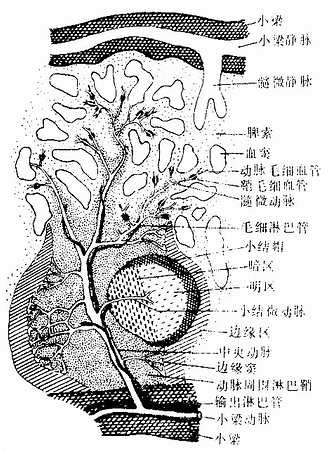

图9-19 脾血液通路模式图

动脉周围淋巴鞘(periarterial lymphatic sheath):是围绕在中央动脉(central antery)周围的厚弥散淋巴组织(图9-18,9-19),由大量T细胞和少量巨噬细胞与交错突细胞等构成。此区相当于淋巴结内的副皮质区,是胸腺依赖区,但无高内皮毛细管后微静脉。中央动脉旁有一条伴行的小淋巴管,它是鞘内T细胞经淋巴迁出脾的重要通道(图9-19)。当发生细胞免疫应答时,动脉周围淋巴鞘内的T细胞分裂增殖,鞘也增厚。

淋巴小结:又称脾小体(splenic corpuscle),结构与淋巴结的淋巴小结相同,主要由大量B细胞构成,发育较大的淋巴小结也呈现生发中心的明区与暗区,帽部朝向红髓(图9-19)。健康人脾内淋巴小结很少。当抗原侵入脾内引起体液免疫应答时,淋巴小结大量增多,它出现于边缘区和动脉周围淋巴鞘之间,使中央动脉常偏向鞘的一侧。

(3)边缘区(marginal zone):位于白髓和红髓交界处,宽约100μm。该区的淋巴细胞较白髓稀疏,但较脾索密集,并混有少量红细胞。此区含有T细胞及B细胞,并含有较多的巨噬细胞。从肌髓或胸腺迁入脾的处女型淋巴细胞常先聚集于此区继续成熟。中央脉侧支分支而成的一些毛细血管,其末端在白髓和边缘区之间膨大形成的小血窦,称为边缘窦(marginal sinus),它是血液以及淋巴细胞进入淋巴组织的重要通道,淋巴细胞也可经此区再迁入动脉周围淋巴鞘、淋巴小结或脾索内。边缘区也是脾内捕获抗原、识别抗原和诱发免疫应答的重要部位,它相当于淋巴结浅层皮质与副皮质的交界处。

脾血窦(splenic sinus):是一种静脉性血窦,宽约12~40μm,形态不规则,相互连接成网。窦壁由一层长杆状的内皮细胞平行排列而构成。内皮细胞之间常见许多0.2~0.5μm宽的间隙,脾索内的血细胞可经此穿越进入血窦(图9-21,9-22)。内皮外有不完整的基膜及环行网状纤维围绕,故血窦壁如同一种多孔隙的栏栅状结构。在血窦的横切面上,可见杆状内皮细胞沿血窦壁呈点状排列,较粗大的内皮细胞断面中可见有细胞核,并突入管腔(图9-19)。血窦外侧有较多的巨噬细胞,其突起可通过内皮间隙伸向窦腔。

2.脾的血液通路 脾动脉从脾门入脾后分支进入小梁,称为小梁动脉(trabecular artery)。小梁动脉分支离开小梁进入动脉周围淋巴鞘内,称为中央动脉。中央动脉沿途发出一些小分支形成毛细血管供应白髓,其末端膨大形成边缘窦。中央动脉主干在穿出白髓进入脾索时分支形成一些直行的微动脉,形似笔毛,故称笔毛微动脉(penicillar arteriole)。笔毛微动脉在脾索内可分为三段(图9-19):①髓微动脉(pulp arteriole),内皮外有1~2层平滑肌;②鞘毛细毛管(sheathed capillary),内皮外有一厚的巨噬细胞鞘,但在人不发达;③动脉毛细血管,毛细血管末端的大部扩大成嗽叭状开放于脾索,少数则直接连通于血窦。血窦汇入由扁平内皮细胞构成的髓微静脉(pulp venule),髓微静脉汇入小梁内的小梁静脉(trabecular vein),最后在门部汇成脾静脉出脾。中央动脉旁的淋巴管沿动脉进入小梁,继而在门部汇集成较大的淋巴管出脾,淋巴内含有许多T细胞。脾内大部分血液流经脾的速度较快,约30秒,少量血液的流速较慢,需数分钟至1小时,依据脾功能状态的不同而有变化。